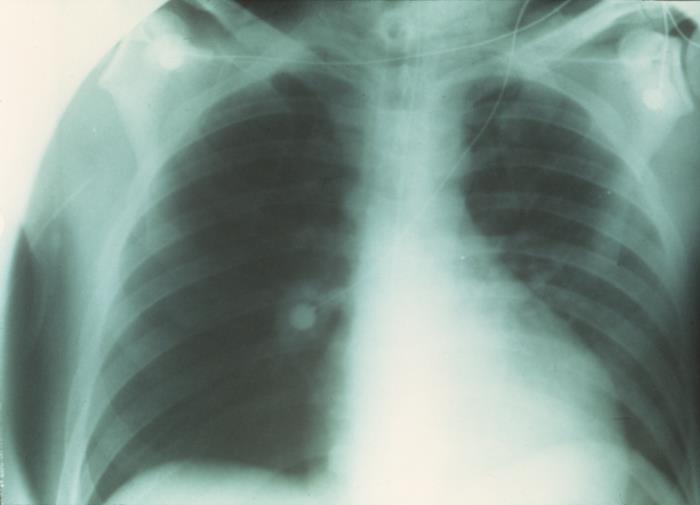

This anteroposterior (AP) x-ray was captured during the resolution phase of a plague infection, revealing the clearing which took place in both lung fields.